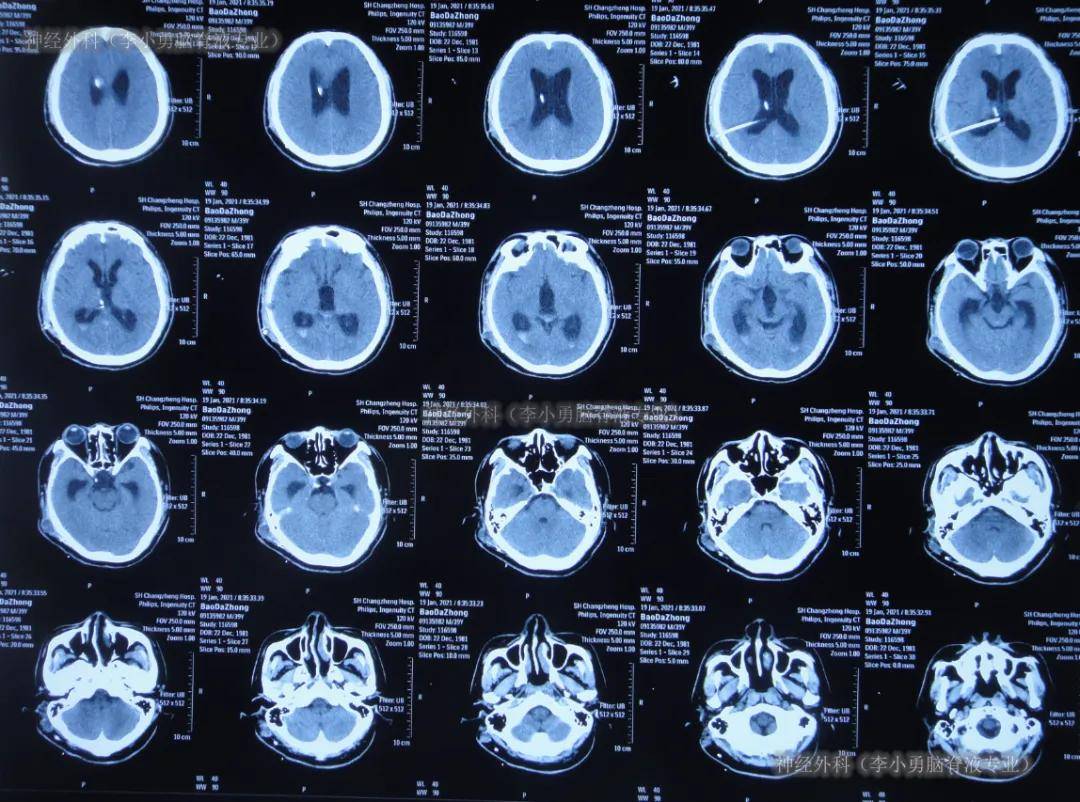

收藏!超详细的头部ct读片详解

图片尺寸1080x648